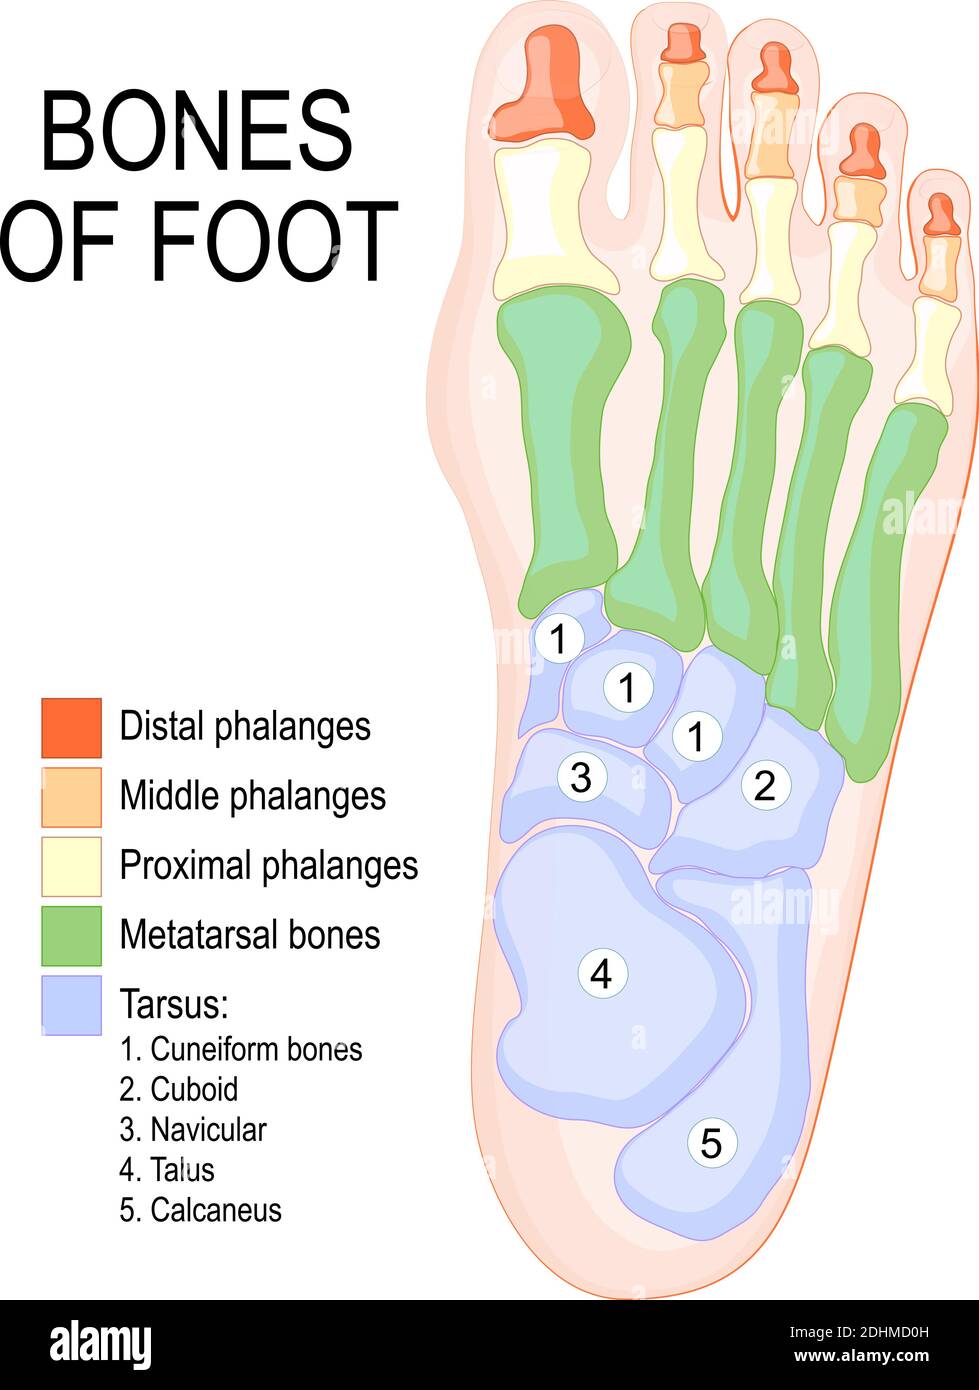

RF2DHMD0H–OS du pied. Anatomie humaine. Le schéma montre l'emplacement et le nom de tous les os du pied.

RF2WWY5XN–Os du pied humain avec le nom et la description de tous les sites. Vue supérieure. Anatomie humaine. Illustration vectorielle isolée sur un fond blanc.

RF2WNN754–Illustration médicale des principales parties des os du pied en vue antérieure, avec annotations.

RF2J65WT4–Anatomie du pied. Pied humain avec le nom et la description de tous les os et sites. Vue de dessus et vue latérale. Arcs des pieds. Anatomie du squelette. Vecteur